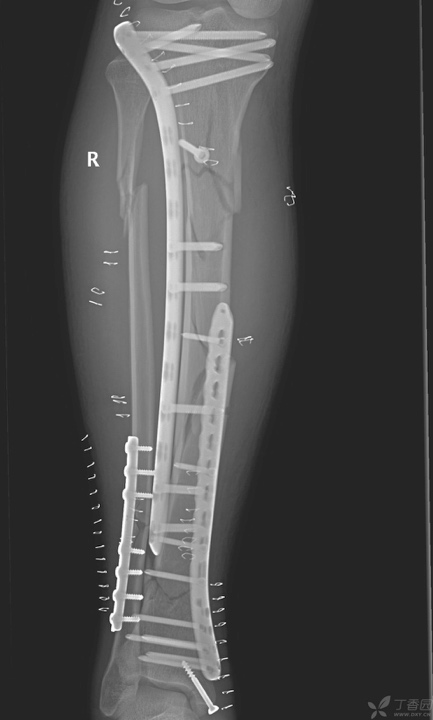

最终选择髌骨上入路髓内钉固定。

技术要点

1、使用牵开器维持骨折端基本的对位,对线。省时,省力不吃射线。

2、近端通过阻挡钉技术辅助骨折断端复位。

3、使用特殊的「 锁定型髓内钉 」远端即便只锁 2 枚锁钉依然稳定。

腓骨采用弹性髓内钉固定

术后复查